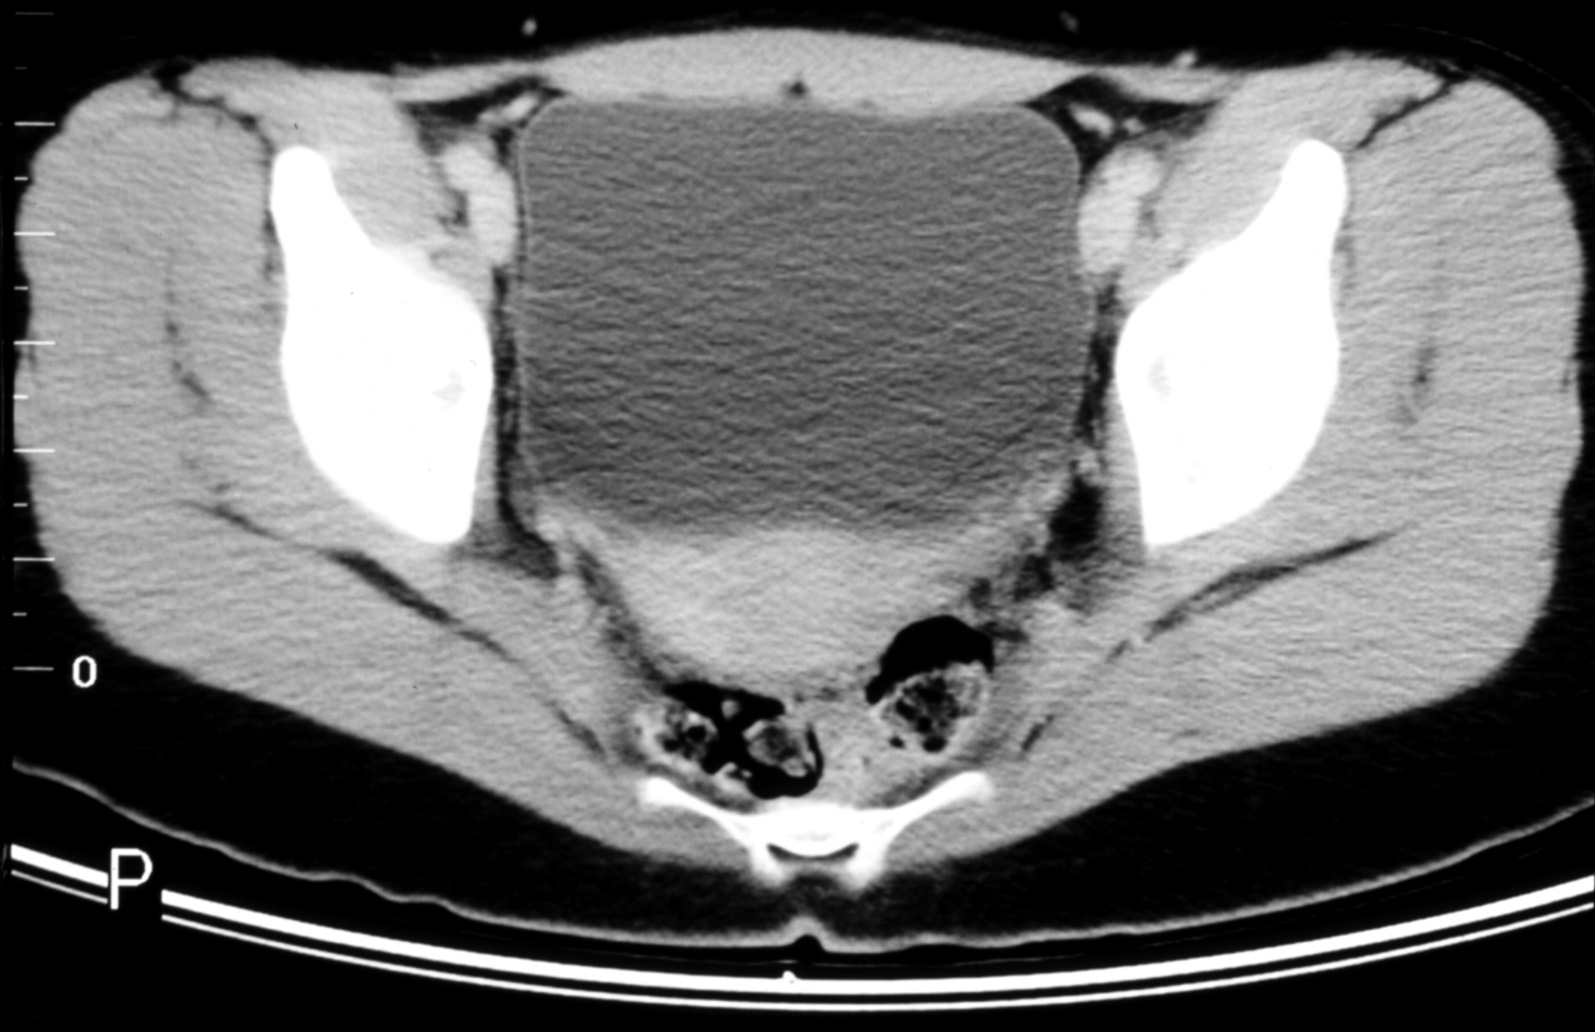

The Structural Basis of Medical Practice

The Pennsylvania State University ©2000

College of Medicine